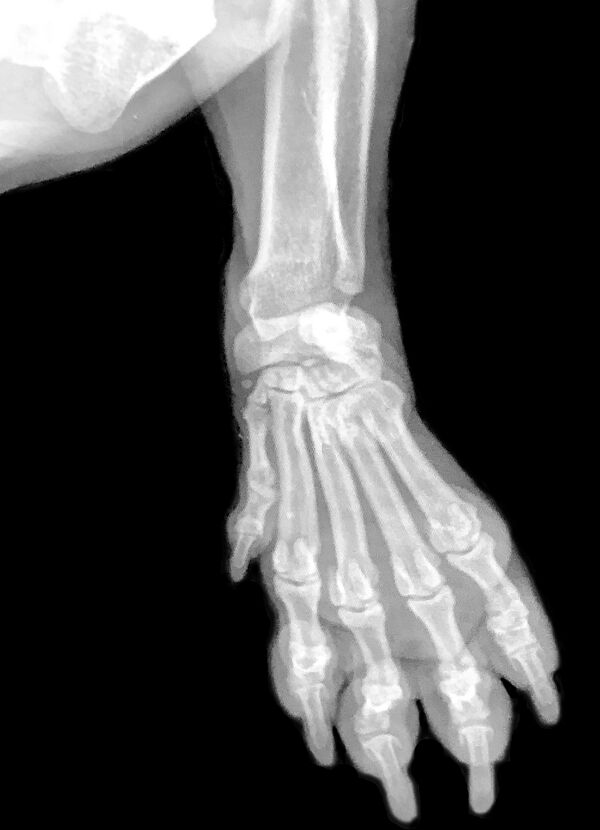

Кости и соединения костей кисти

Скелет кисти составляют кости запястья, кости пясти и кости пальцев (фаланги). Запястье состоит из восьми коротких губчатых костей, расположенных в два ряда, по четыре в каждом ряду:

- верхний: ладьевидная (os scaphoideum), полулунная (os lunatum), трёхгранная (os triquetrum), гороховидная (os pisiforme);

- нижний: кость-трапеция (os trapezium), трапециевидная (os trapezoideum), головчатая (os capitatum), крючковидная (os hamatum) кости[1].

Следующий ряд костей кисти образуют пястные кости. Костей пять, по числу пальцев. Основания их соединяются запястными костями. Фаланги пальцев так же, как и пястные кости, являются короткими трубчатыми костями. В каждом пальце имеется по три фаланги: основная (проксимальная), средняя и концевая или ногтевая (дистальная). Исключение составляет большой палец, который образован только двумя фалангами — основной и ногтевой. Между пястной костью и фалангами каждого пальца образуются подвижные сочленения.

Кисть имеет три отдела: запястье (carpus), пястье (ossae metacarpi) и пальцы (digitus mani)[2].

Пясть состоит из пяти трубчатых пястных костей. Пястная кость первого пальца короче остальных, но отличается своей массивностью. Наиболее длинной является вторая пястная кость. Следующие кости по направлению к локтевому краю кисти уменьшаются в длине. Каждая пястная кость имеет основание, тело и головку.

Каждый палец состоит из трёх фаланг: проксимальной, средней и дистальной. Исключение составляет первый палец, имеющий только две фаланги — проксимальную и дистальную. Проксимальные фаланги являются наиболее длинными, дистальные — наиболее короткими. Каждая фаланга имеет среднюю часть — тело и два конца — проксимальный и дистальный. На проксимальном конце находится основание фаланги, а на дистальном — головка фаланги. На каждом конце фаланги имеются суставные поверхности для сочленения с соседними костями.